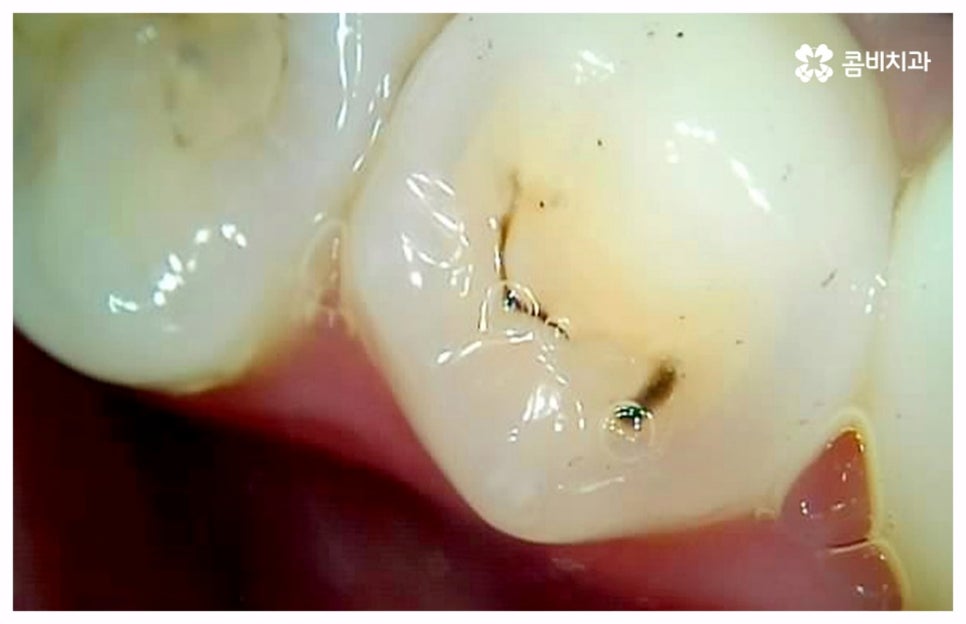

충치나 잇몸 질환은 보통 단계적으로 서서히 발전하기 때문에 환자분들께서 하루 아침에 극심한 통증을 느끼게 되는 경우는 많지 않지만 혹시라도 갑작스럽게 치통이 심할때 혹은 밤에 자려고 누웠는데 더욱 치통이 심할때 는 급성치수염을 의심해 볼 수 있어요. 급성치수염은 언급했던 충치나 외상성 치아 파절로 인해 치아 가장 안 쪽에 있는 치수 부분까지 세균이 침투하여 염증이 발생하는 것을 의미하는데, 이 때 감염된 혈관이 부어오르면서 단단한 치아 외벽에 둘러쌓인 치아 내부 압력이 올라가 작은 움직임에도 극심한 통증을 느끼게 되는 거예요.

급성치수염에 대한 치료는 보통 안쪽까지 침투한 세균을 깨끗하게 긁어내고 염증 및 괴사된 치수 부분을 삭제한 다음 뿌리관(근관)을 소독하고 치과 충전물로 밀봉하는 신경 치료를 통해 이루어지는데, 이렇게 신경 치료를 진행하고 나서 후속 치료로서 남아있는 자연 치아를 보호하고 저작 기능을 제대로 수행할 수 있도록 하기 위해 주변 치아와 크기, 높이 등을 맞추어 딱 맞게 제작한 보철물을 덮어씌우는 크라운 치료를 해 주는 것이 자연 치아를 보다 오랜기간 동안 건강하게 사용할 수 있도록 하는데 크게 도움이 된다고 할 수 있어요. 경우에 따라서 앞니의 경우 신경관이 많지 않기 때문에 레진으로 치료를 마무리하는 경우도 있으니 참고해 주시면 좋을 것 같아요.